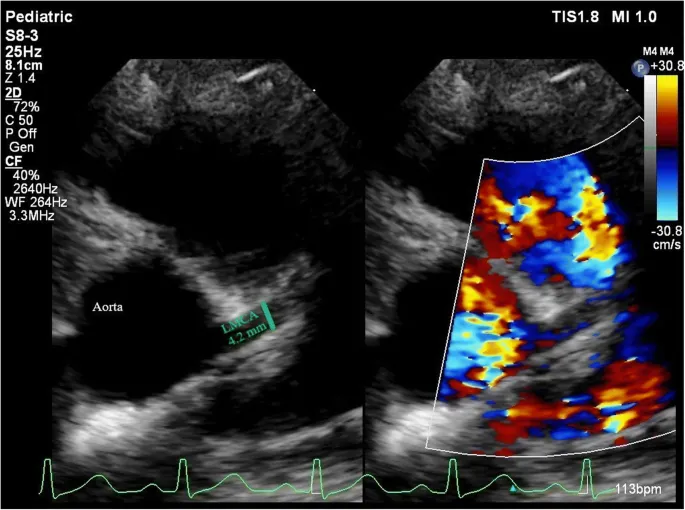

Echocardiographic Evaluation - Heart Detective Work

Primary Goal: Detect coronary artery abnormalities (CAA), primarily aneurysms, and assess myocardial function.

- Coronary Arteries: Dilatation, aneurysms (saccular/fusiform), thrombosis. Measured in LAD, RCA, LCx.

Z-Scores (Body Surface Area-Adjusted):

- No dilatation: Z-score < 2

- Dilatation only: Z-score ≥ 2 to < 2.5

- Small aneurysm: Z-score ≥ 2.5 to < 5

- Medium aneurysm: Z-score ≥ 5 to < 10

- Large/Giant aneurysm: Z-score ≥ 10

⭐ Giant aneurysms (Z-score ≥ 10 or absolute dimension >8 mm) carry the highest risk of thrombosis and stenosis.